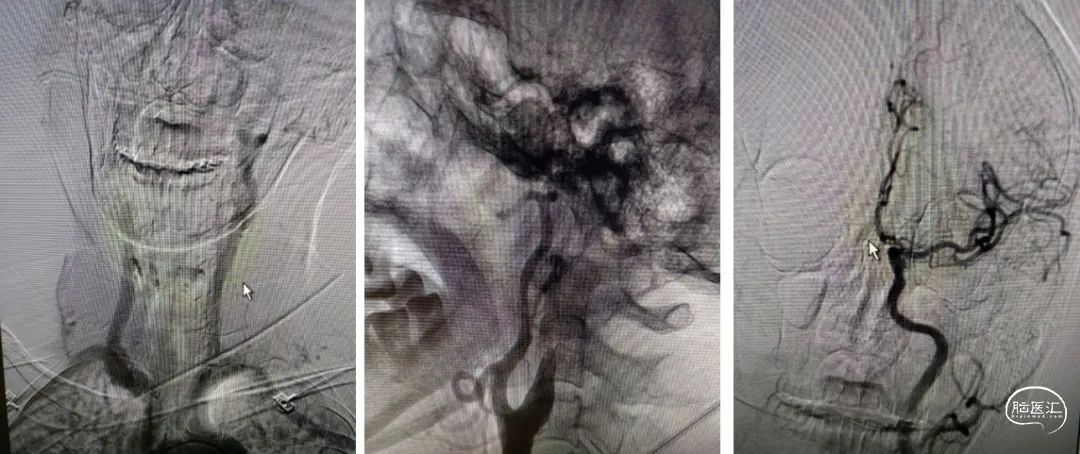

6F-远端通路导管在黑泥鳅导丝的指引下通过闭塞段送至眼动脉段,造影证实闭塞段在海绵窦段,予以ADPAT技术取出少量血栓,仍未开通。

通过微导管释放取栓支架,SWIM取栓技术,可见海绵窦段狭窄,前向血流不稳定。

利用PTA球囊导管对狭窄处进行扩张,可见狭窄明显改善,但眼动脉段以后闭塞,再次将取栓支架予以取栓,可见斑块逃逸至M1段。

多次利用取栓支架SWIM技术对逃逸斑块进行取栓但未成功。

治疗中影像

Guiding到位,导丝通过病变。

球囊通过病变。

球囊扩张过程。

扩张后造影。